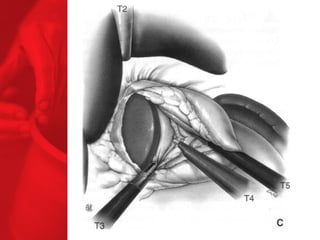

GASTRIC BYPASS Lesprocédures de malabsorption et restrictives > 56% de perte de poids excédentaire après quatre ans* > diminue le diabète de type 2 chez plus de 83 % des patients* *Christou NV, Sampalis JS, Liberman M, et al. Surgery Decreases Long-Term Mortality, Morbidity, and Health Care Use in Morbidly Obese Patients. Annals of Surgery 2004;240(3):416-424. ** Buchwald H, Avidor Y, Braunwald E, et al. Bariatric Surgery—A Systematic Review of the Literature and Meta-analysis. Journal of the American Medical Association 2004 Oct 13;292(14).

Echecs Malgré unebonne technique du CCGL, des échecs surviennent chez 15 à 20 % des patients. Les causes de reprise pondérale sont la dilatation de la poche gastrique, la dilatation de l'anastomose gastrojéjunale, l'hypertrophie des villosités du jéjunum proximal et la prise d'une alimentation avec des liquides à haute teneur en calories. Ainsi, pour les « superobèses » pathologiques (IMC > 50 kg/m2), l'intervention de référence pourrait devenir la diversion biliopancréatique.

COMMENT FONCTIONNE LECOURT-CIRCUIT GASTRIQUE ? Facteurs chirurgicaux Restriction du volume des repas Certaine malabsorption Syndrome de chasse Réduction de l'appétit Facteurs pour les patients Apport en calories Dépense en calories BILAN ENERGETIQUE = apport alimentaire dépense en énergie